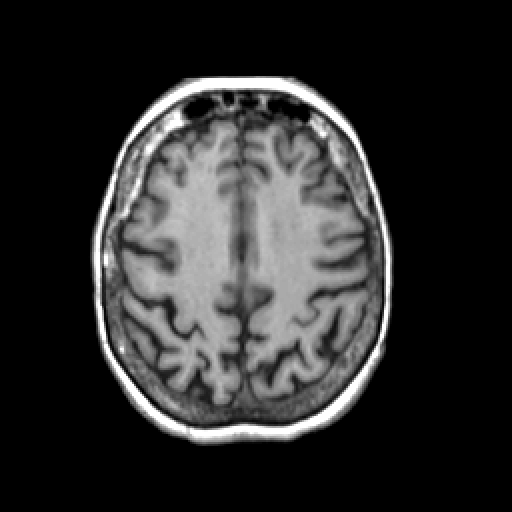

T1-weighted structural MR: Slice 37

Slice 37